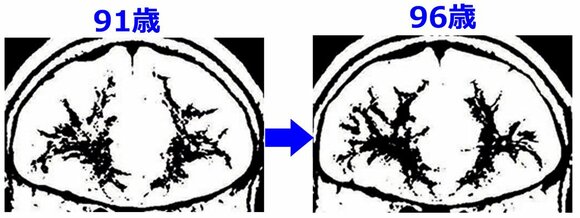

●90歳を過ぎても進化する吉沢さんの脳

吉沢さんの脳のMRI画像を、年齢で比べたものがこちら。思考をつかさどる、前頭葉の先端部分・超前頭野(思考系脳番地)を通過する神経線維の枝ぶりが、右脳、左脳ともに太く成長しているのがわかります。 ※出典:『家事で脳トレ65』 主婦の友社刊